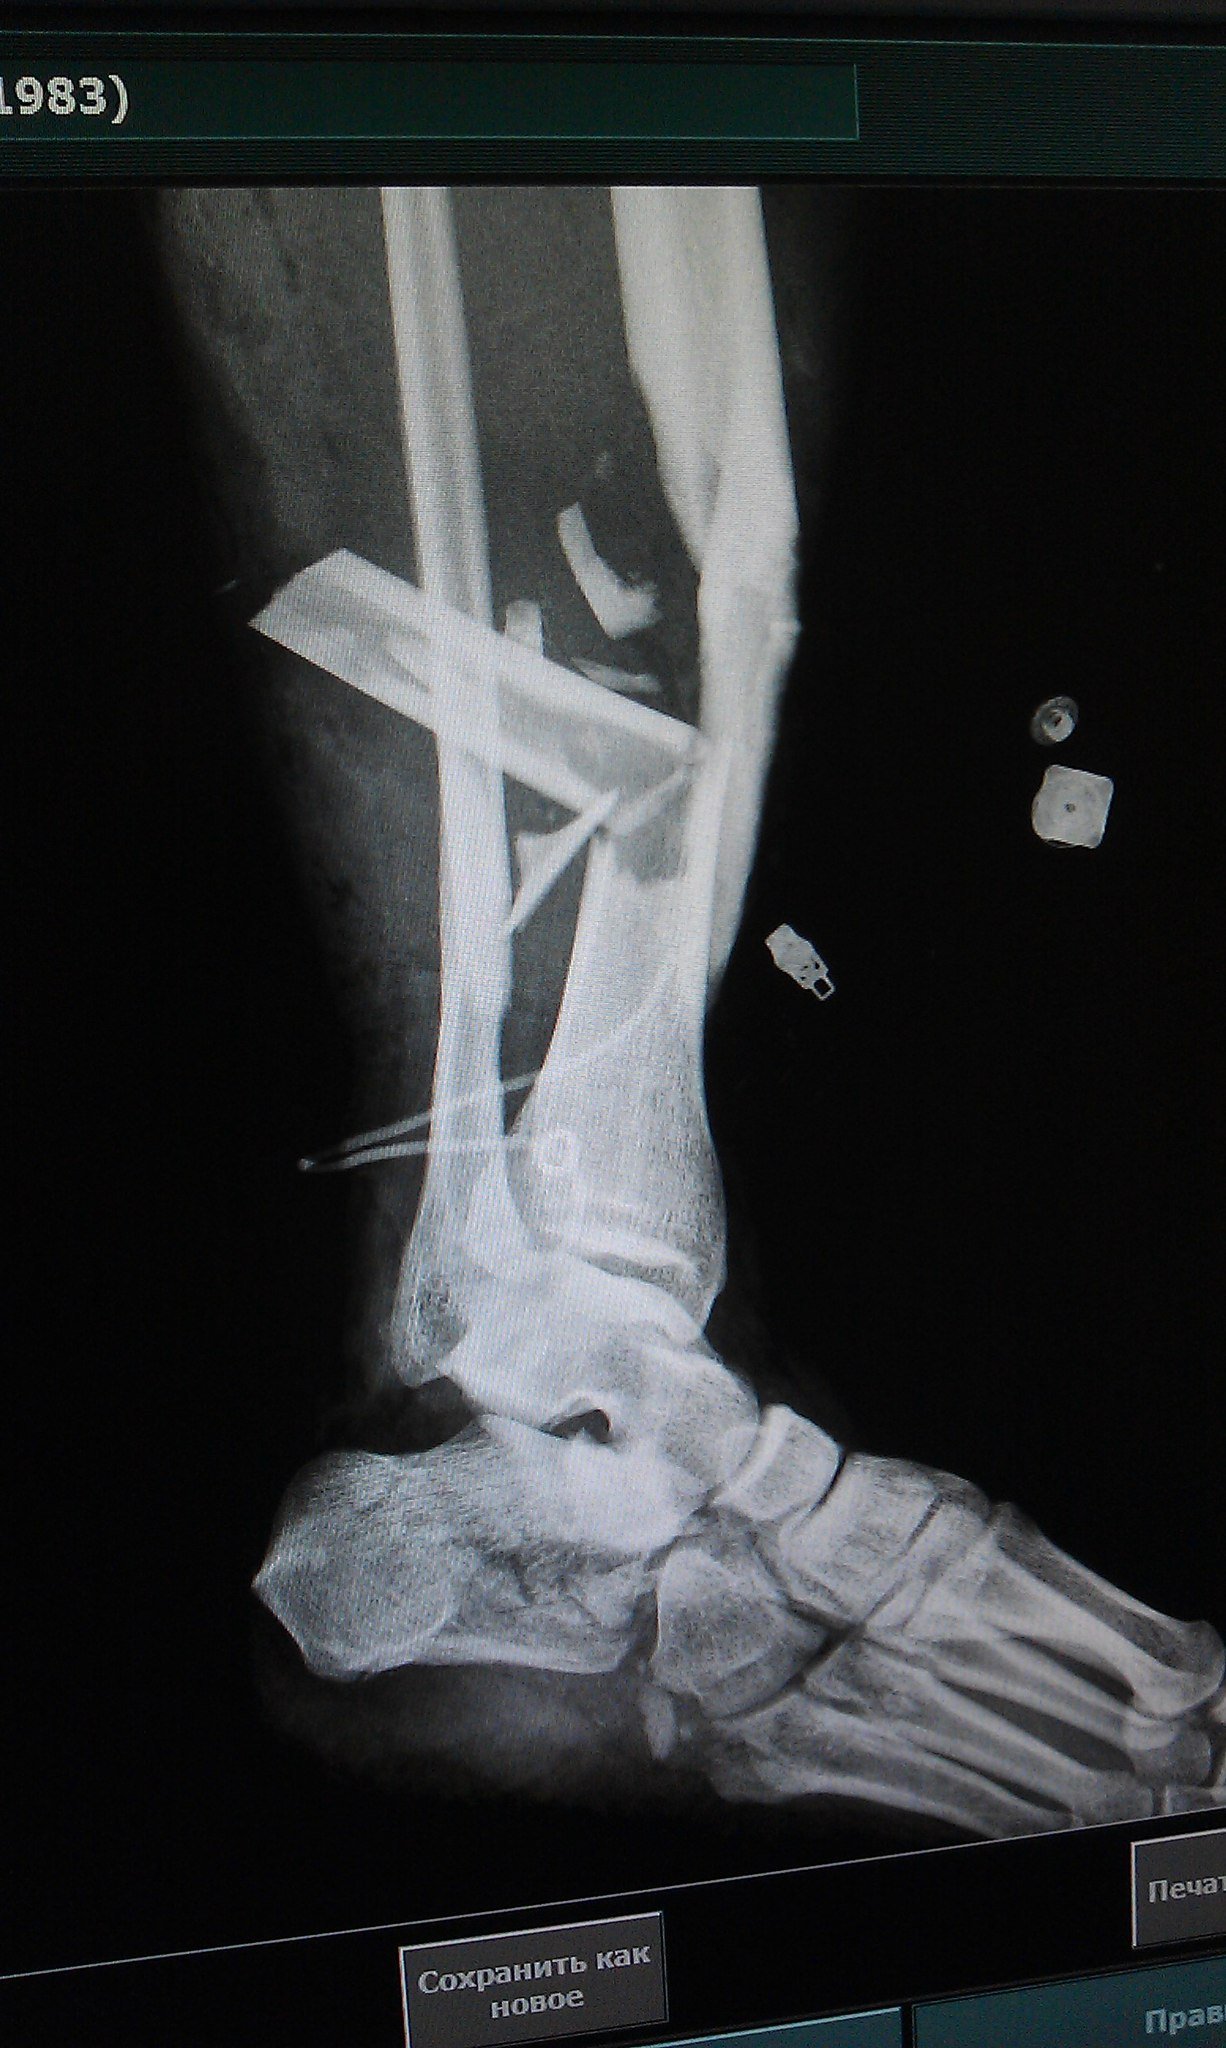

Эпикриз: Сочетанная травма. ЗЧМТ. Сотрясение головного мозга. Открытый многооскольчатый перелом обеих костей с/3 правой голени со смещением отломков. Открытый многооскольчатый перелом пяточной, ладьевидной, кубовидной кости, подвывих пяточной кости. Обширные рваные раны области правой стопы, правой голени.

было это еще 7 июня, но до сих пор, по прошествии двух операций ему не собрали все кости. Оказалосьь, что одну кость забыли на месте ДТП и теперь вместо нее требуется имплант. На одной ноге у него сейчас 18 переломов и 3 из них гниют, один из кусков кости встал поперёк, врачи опасаются её доставать или разворачивать, ибо можно занести ещё больше инфекции, если делать, то надо делать сразу всё комплексно, а пока приходится постоянно чистить, чтоб не было заражения, никакие обезболивающие уже не помогают, организм уже к ним адаптировался, и приходится терпеть эти боли. Нам же остается только медленно собирать деньги.